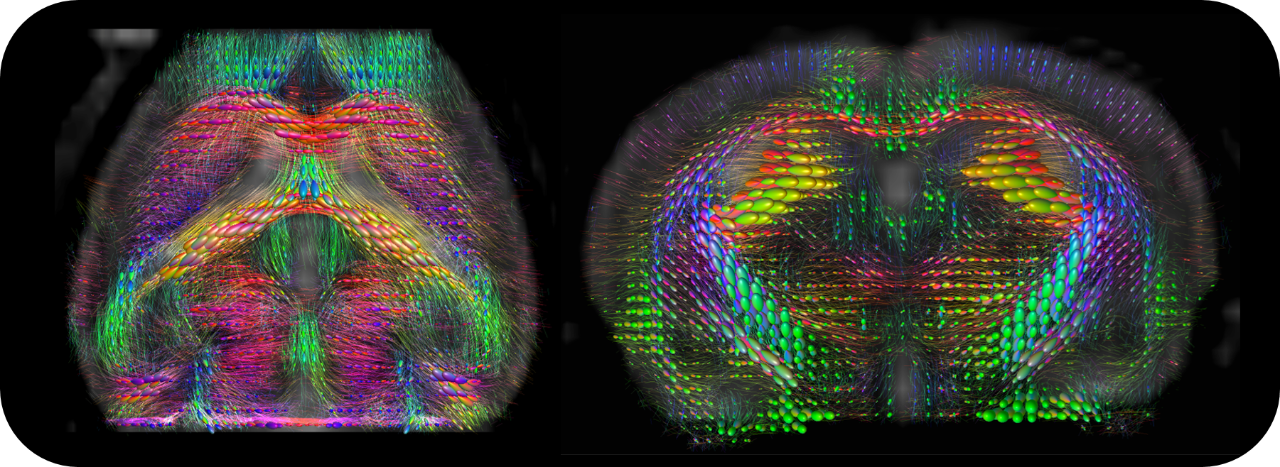

BioSpec 70/30 and 94/30

Studies with intricate set-ups or on animals up to the size of rabbits can be conducted with the extremely physically stable, 30 cm bore size BioSpec 70/30 and BioSpec 94/30.

• MRI sequence portfolio of more than 1,000 sequence variations, including wireless cardiac imaging using navigator based IntraGate methods with cartesian or radial readout, as well as short echo time imaging, such as UTE and ZTE

PET Insert or Inline

Upgradable with state-of-the-art PET module as inline or insert with full field of view and accuracy offers real, homogeneous sub-millimetric volumetric PET resolution and quantification in all three axes, in the entire field of view. This is possible due continuous crystal detectors with SiPM technology and true depth of interaction 3D precision equivalent to 10+ layer pixelated crystal detectors.